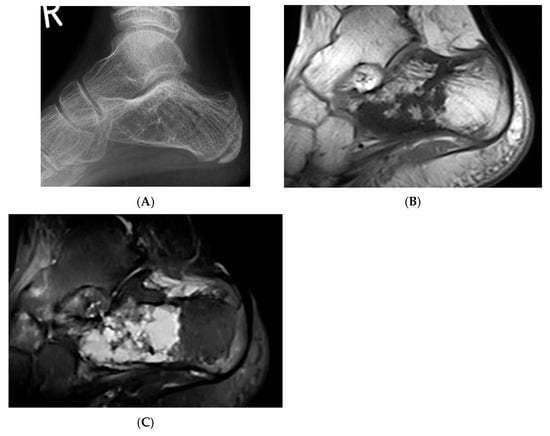

Figure 3.

Intraosseous lipoma, calcaneum. (A) Plain radiograph demonstrating the classic location of the lesion with “bull’s eye” sign (solid white arrow). (B) Sagittal T1W MRI with fat-containing lesion.

Advanced stages of the lesion may show central or peripheral calcification, described as a distinctive “bull’s-eye” appearance, or ossification, occasionally mimicking enostosis, chondroid lesions, or osteonecrosis. Asymptomatic lesions require no treatment, whilst symptomatic cases may be treated with curettage and bone grafting. Recurrence and malignant transformation are rare.

Figure 5.

Haemangioma, calcaneum. (A) Plain radiograph demonstrating honeycomb pattern. (B) Sagittal T1W MRI and (C) sagittal STIR MRI demonstrating intralesional fat component (low T1 and high STIR) and septations.